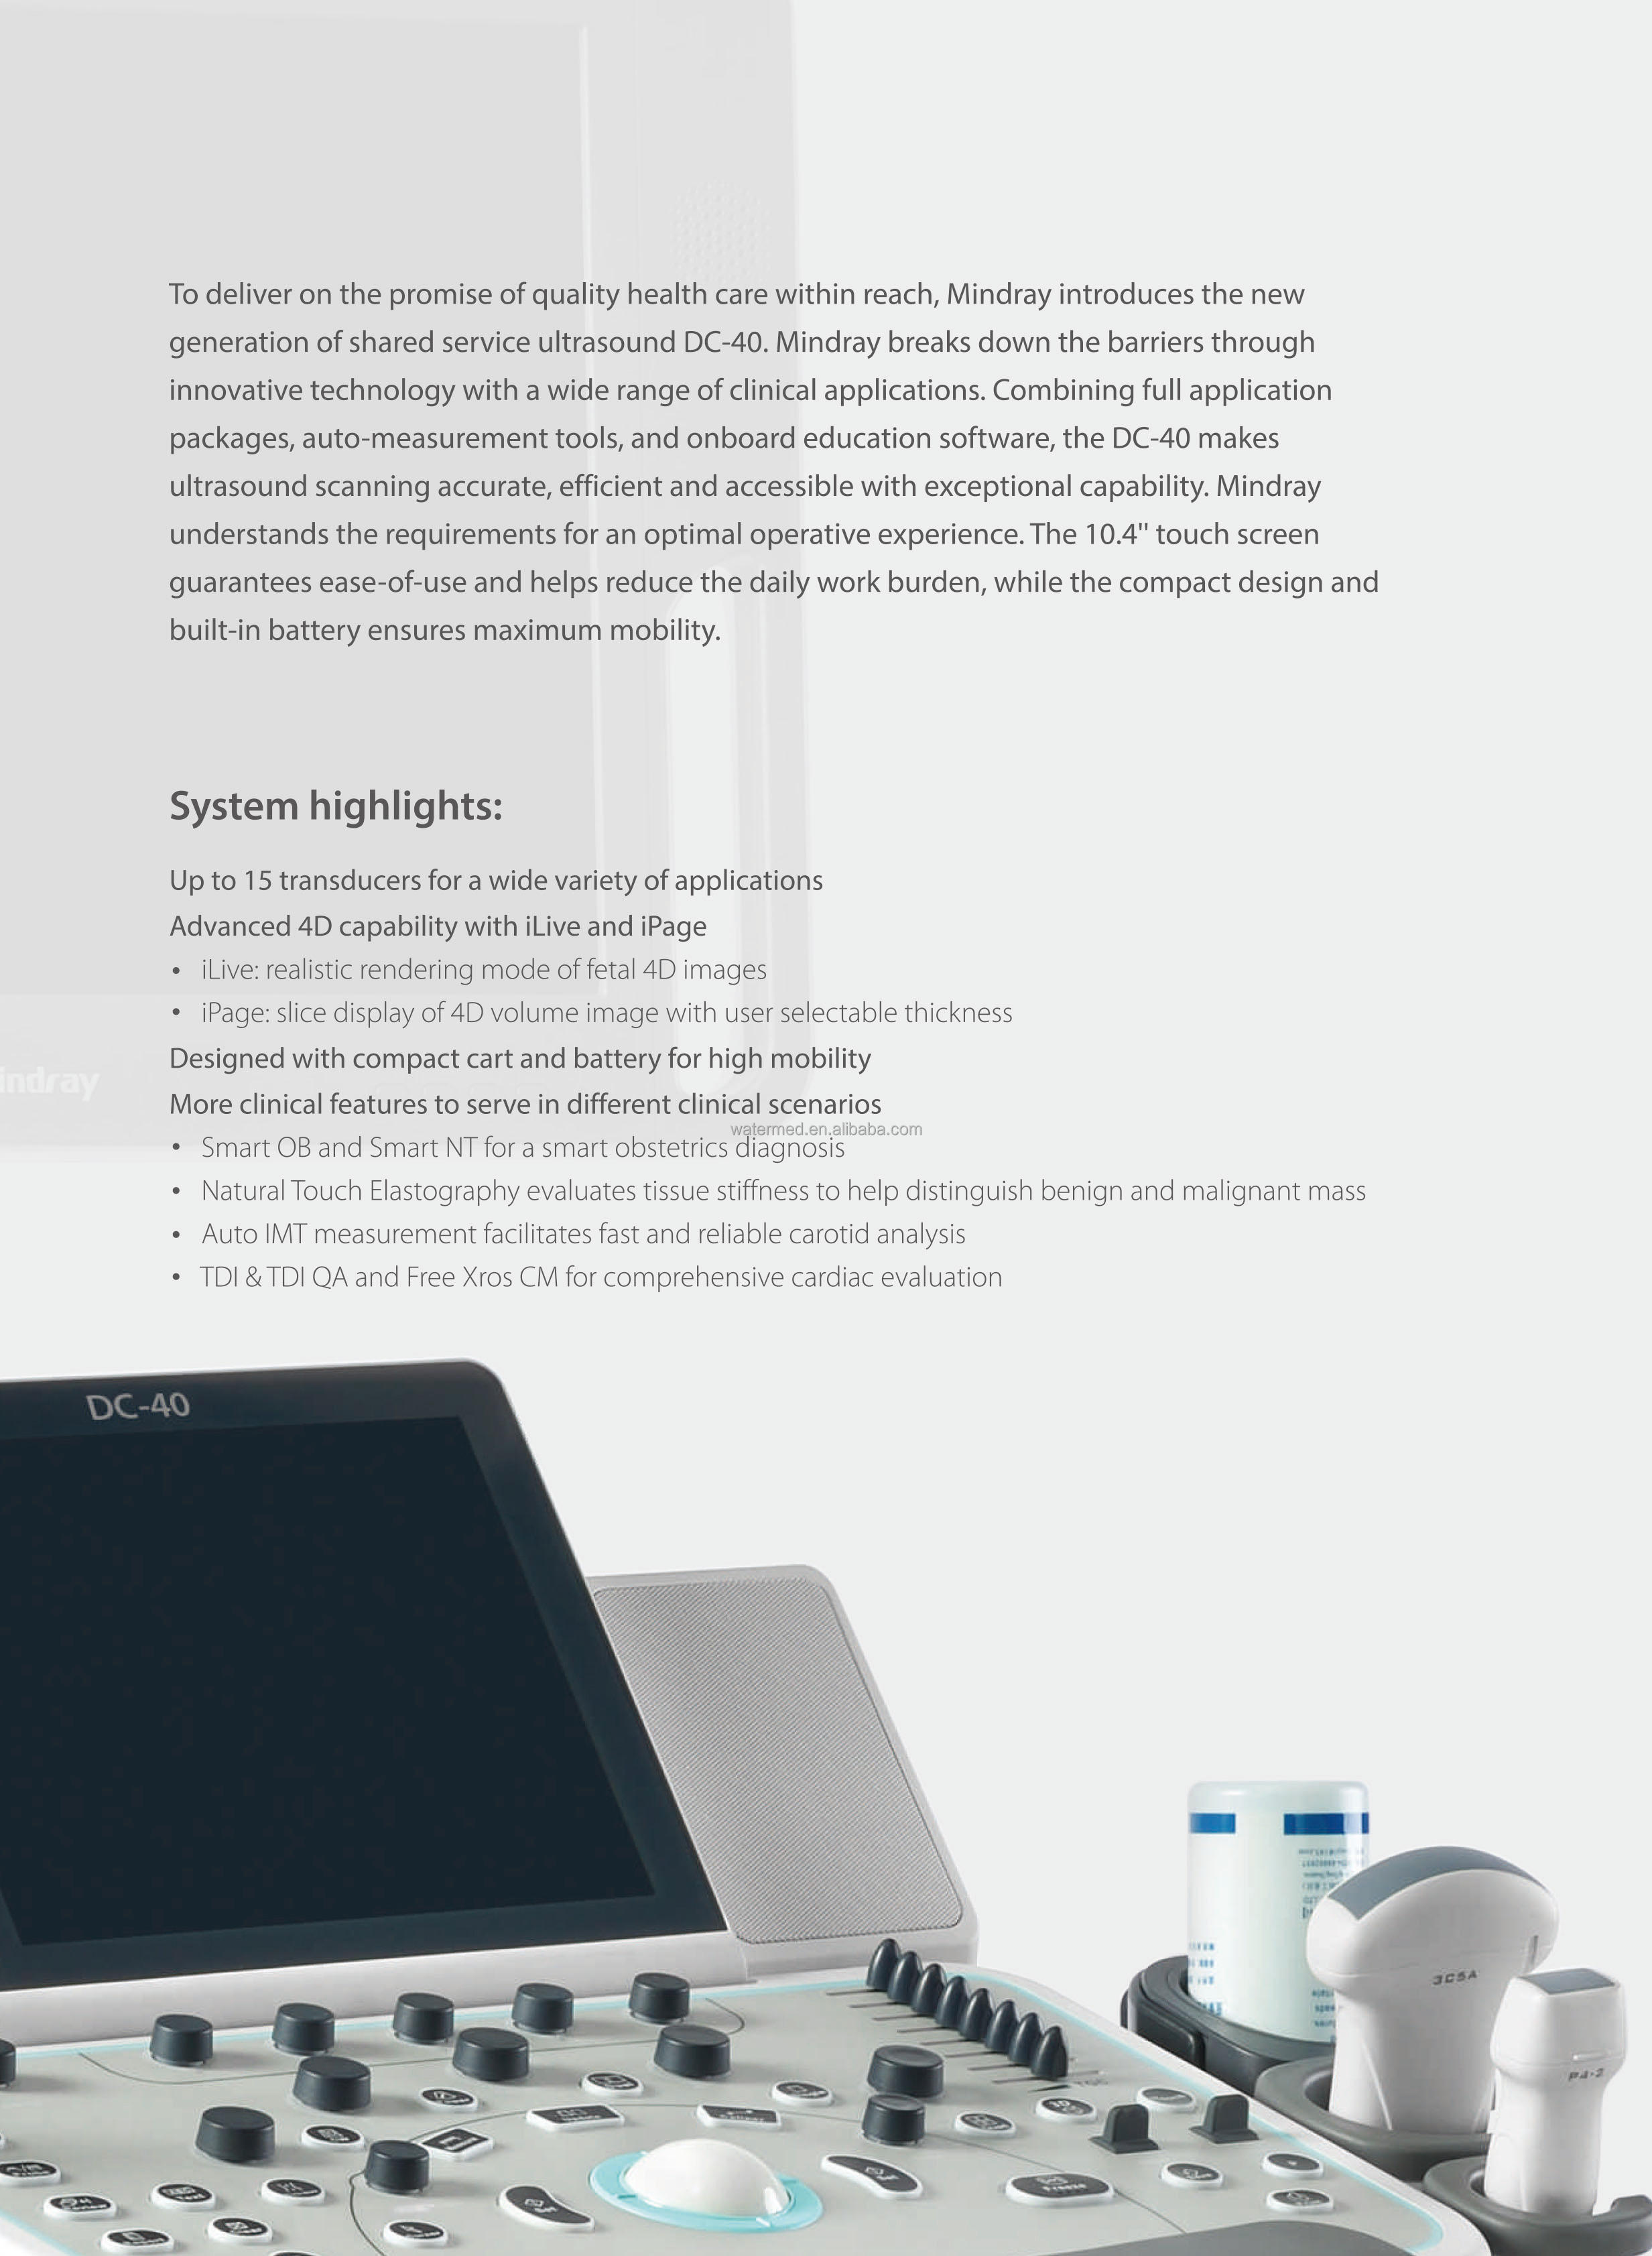

Available Mindray 4D Ultrasound DC-40 Mindray Cart

feature

Tissue Harmonic Imaging: Yes

Spatial compounding (=CrossXbeam): Yes (iBeam)

Speckle Reduction (=SRI): Yes (iClear)

Automatic Image Selection (B Mode): Yes (iTouch)

Automatic Image Selection (Doppler): No

Write Zoom: Yes (iZoom)

Triple Mode: Yes

Needle Enhancement or Needle Identification: Yes (iNeedle)

Automatic NT measurement (=Sono NT): Yes (Smart NT)

Automatic Follicle 2D Measurement: No

Automatic Hair Follicle 3D Measurement: No

Automatic IMT: Yes

- Auto IMT (Real Time): No

Automatic B/M/D Measurement: No

Automated LH measurement (Automatic Functional Imaging (AFI), Cardiac Motion Quantification (CMQ) or Automated EF (Ejection Fraction): Yes

Real-time dual (B/BC) mode: Yes

SmartExam or Scan Assistant: Yes (iWorks)

Fusion: no

Raw data files: yes

Flexible reporting: yes

Barcode Reader: Yes

Gel warmer: yes